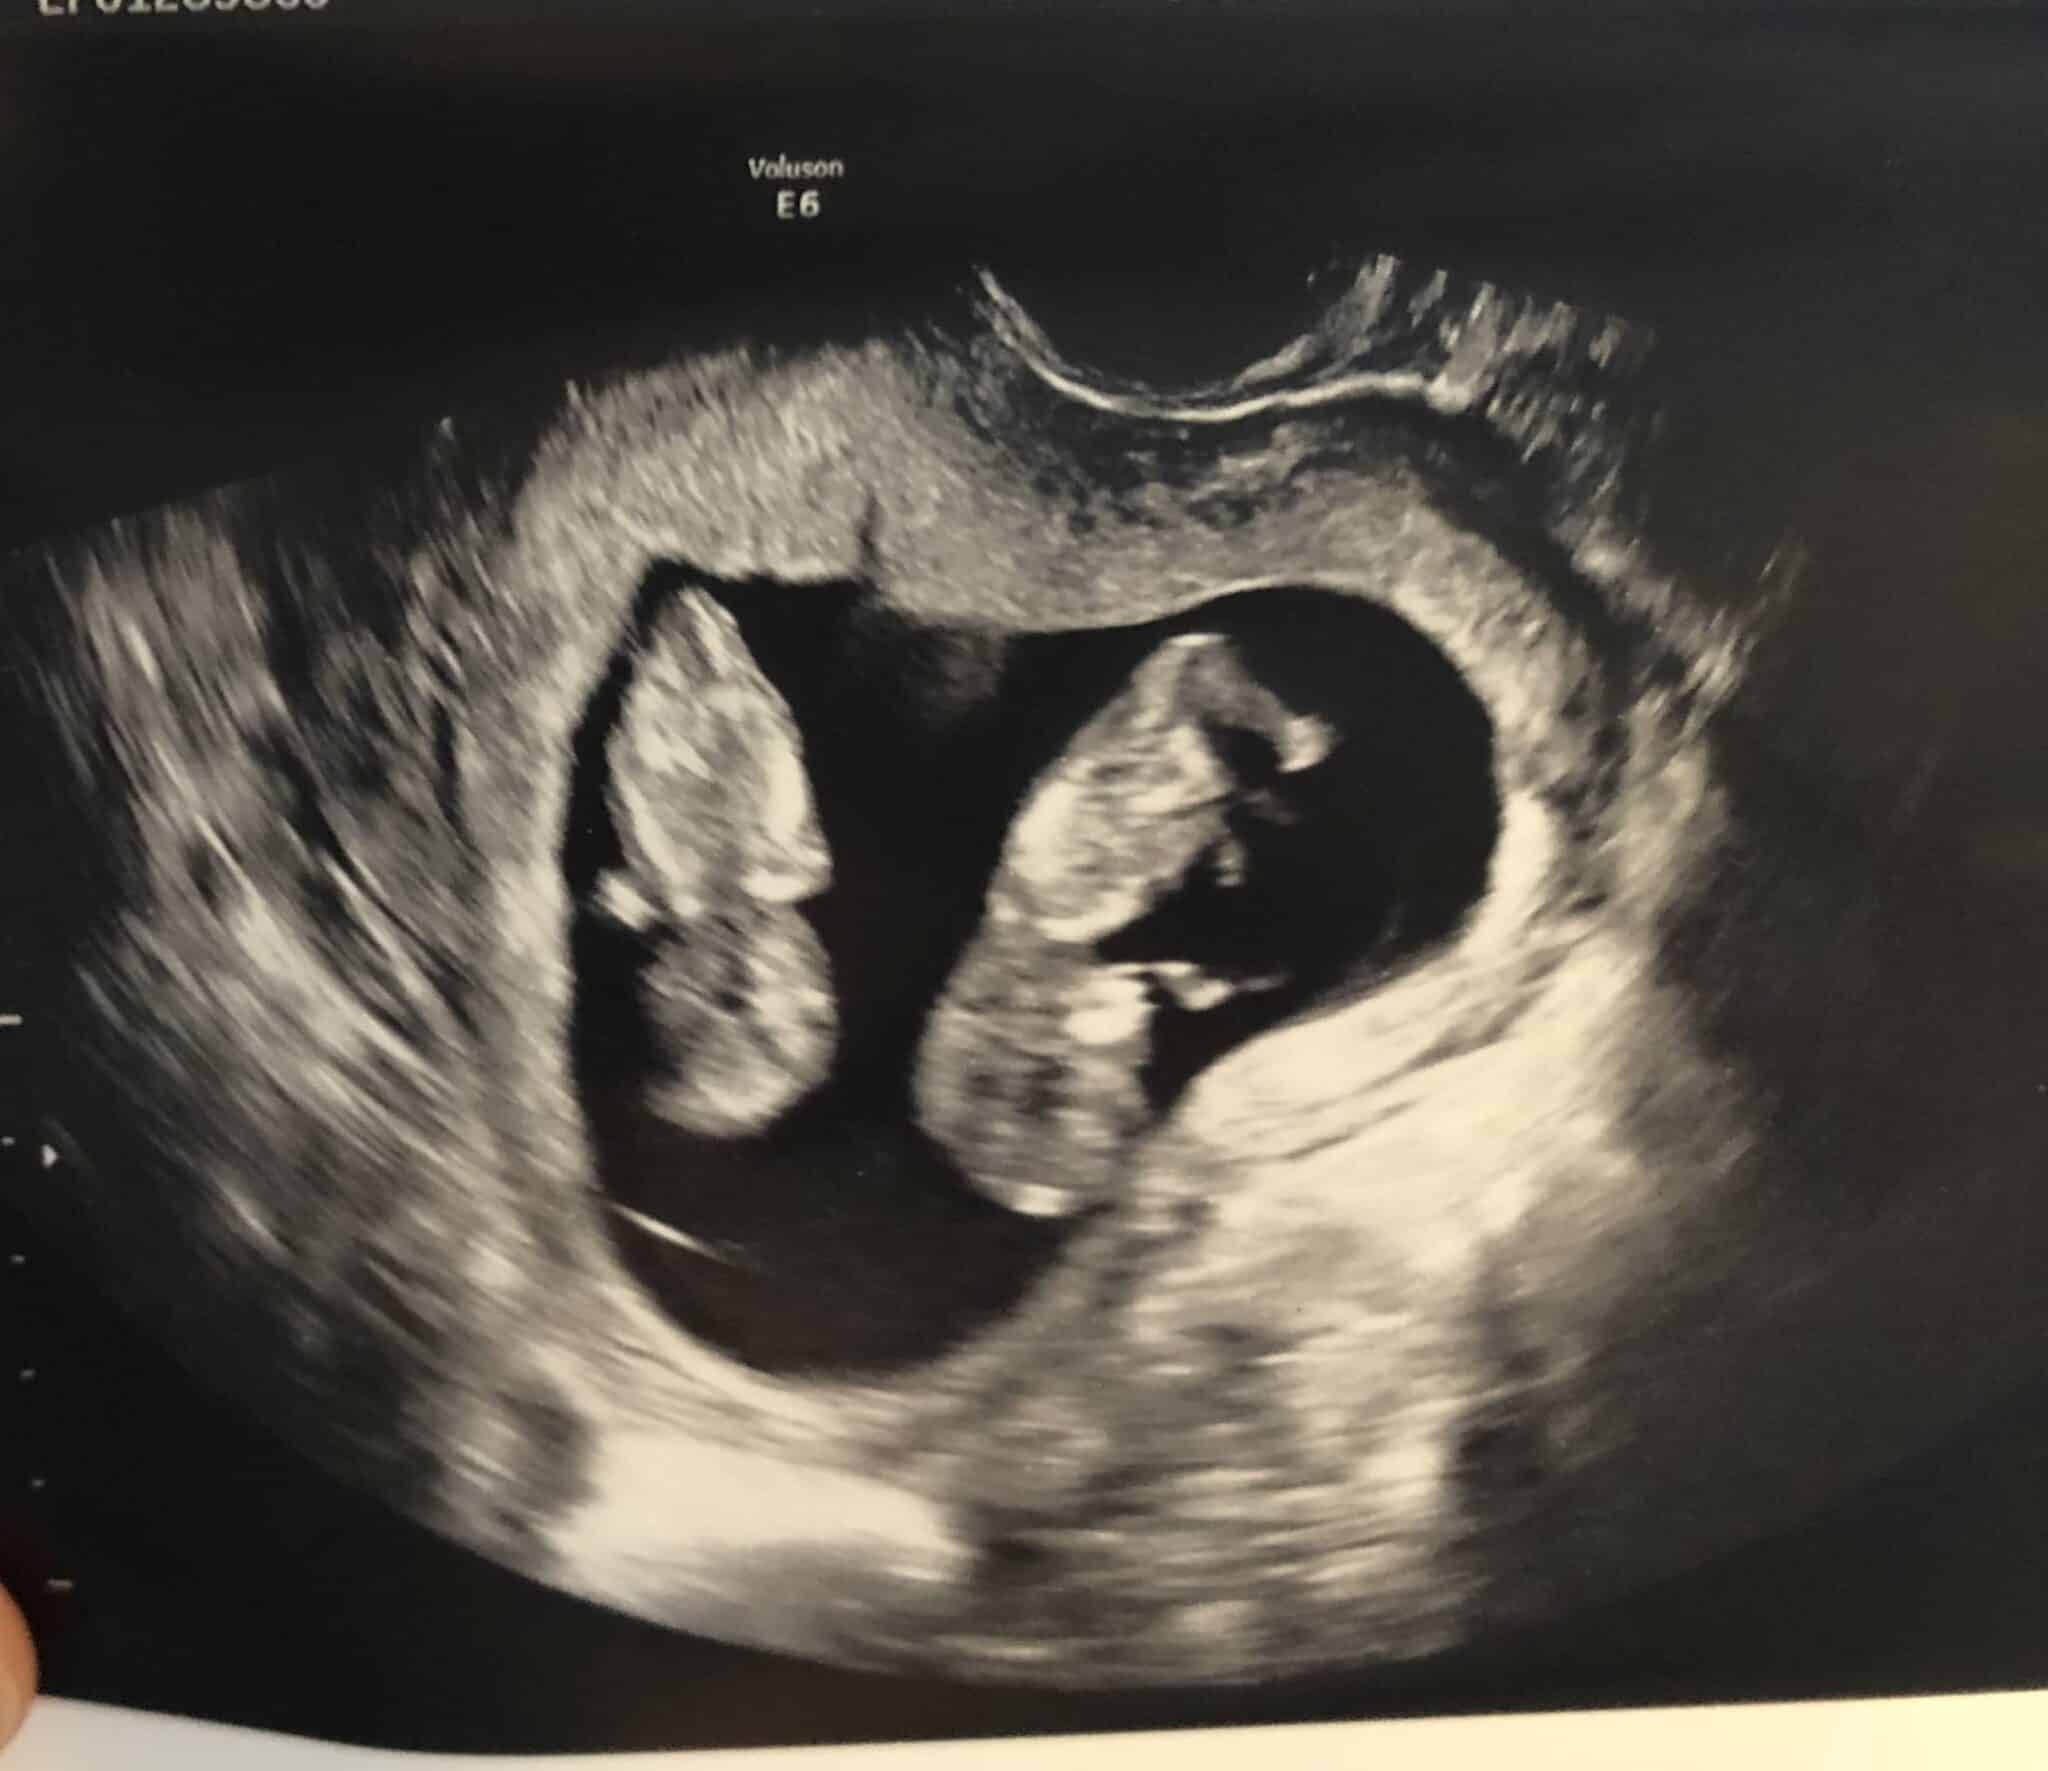

Ultrasound Photos at 11 Weeks Pregnant With Twins